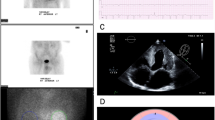

A standardized 16-segment echocardiographic short axis model described by the American Society of Echocardiography (ASE) [36] was used as a starting point to define regions to quantify. Because coronary perfusion territories were not relevant for the study, the model was simplified. Mapping modifications were conducted as described in Fig. 1. The mapped heart structures included LV lateral wall, interventricular septum (IVS), apex of the heart (Apex), and RV free wall (Fig. 2). RV free wall was mapped like the other VOIs, but in some cases, parts of the RV free wall directly adjacent to sternum were excluded from the VOI to avoid spill-over from the sternum. This was carried out by identifying and adding a border around the sternum, to minimize the influence of sternum spill over (Fig. 2). All heart-related quantification mappings were done in the cardiac short axis projections.

Different regions are presented in the following colours: purple—right ventricular free wall (RV free wall); yellow—interventricular septum (IVS); blue—apex of the heart (Apex); orange—left ventricular lateral wall (LV lateral wall). The definition of these follows stepwise. A. Description of the echocardiographic 16-segment short axis bulls eye model. B. Regions used in the study. The anterior segments [1, 7] and the posterior segments [4, 15] were split in half and joined with their respective side. C. Regions used to compare uptake against echocardiographic strain: red—left ventricle (LV), purple—right ventricular free wall (RV free wall). D. Region used to compare uptake against cardiac biomarkers: green—heart ventricles (whole heart)

DPD-SPECT slices in apical short axis view (top panels) and apical long axis view (bottom panels) demonstrating volumes of interest (VOIs) mapping and sternum isolation from the right ventricular wall for minimizing the sternal activity spill-over. Different VOIs are presented in colours as defined in Fig. 1. Purple—right ventricular free wall (RV-free-wall); yellow—interventricular septum (IVS); blue—apex of the heart (Apex); orange—left ventricular lateral wall (LV lateral wall); red—left ventricle (LV); green—heart ventricles (whole heart); mustard yellow—boarder around sternum; turquoise—sternum spill over

The speckle tracking strain analyses were conducted according to ASE guidelines from the apical four-chamber view, during systole [36]. End systole was defined by mitral valve motion from anatomic M-mode or from T-wave from the superimposed electrocardiography. RV free wall strain and GLS analysis of LV were done manually by tracing the endocardial borders. ROIs were automatically defined by the software. Papillary muscles were excluded in all strain measures as per the ASE guidelines. When needed, segments were manually adjusted after the automatic ROI generation, and insufficient ROIs were excluded. Due to thickened ventricular walls, ROI analysis on the full wall thickness was not always possible and was often adjusted manually. Matching of ROI segments with DPD VOIs is described in Figs. 1, 2, and 3. For normal values, values from the European Association Cardiovascular Imaging were used [39].

Images of echocardiographic speckle tracking strain analysis in apical four-chamber view projections. Top panels show full wall regions of interest (ROIs) mappings for left ventricular global longitudinal strain (LV) (left) and right ventricular free wall strain (RV free wall) (right). Bottom panels show how different echocardiographic ROIs match the DPD scintigraphic volumes of interest (VOIs) described in Fig. 2